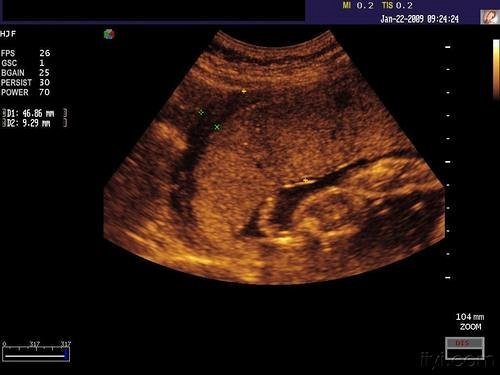

老化和钙化不同。胎盘老化指它的成熟度。一共分为三个阶段。从宝妈怀上孩子的第七个月,医生就要开始检测胎盘的情况了。它的成熟度和宝宝的发育情况息息相关。

在孕早中期,大部分都处于1度或2度,正常情况下,分娩前处于3度。如果处于3度状态的话就说明胎盘出现了老化。

当它在3度的时候,说明它已经成熟了,所能提供给孩子的营养已经达到了最大值,过了这个阶段,它能够提供的营养,以及其本身的质量已经开始退化、走下坡路了。胎儿无法从中得到足够的营养,影响其发育。2、3度来得越快,意味着母子需要承担的风险就越大,必须引起重视。